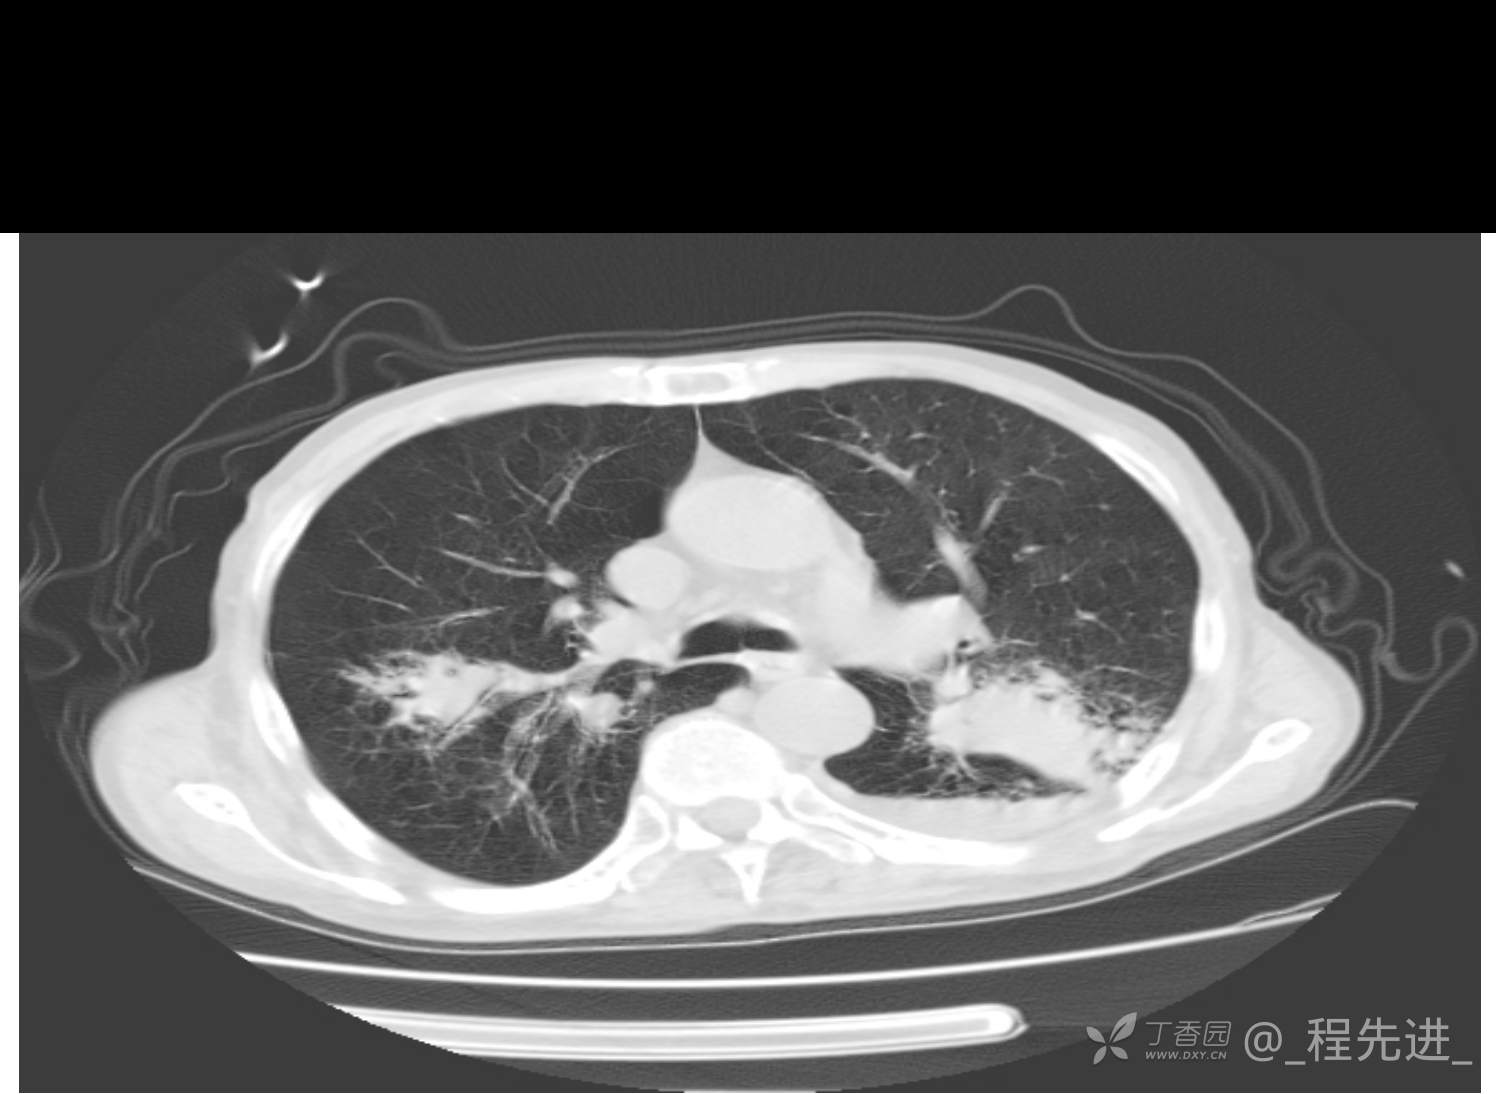

患者性别:男

患者年龄:81岁

简要病史:反复咳嗽、咳痰20余年,加重1周。两肺呼吸音低,可闻及散在干湿啰音。